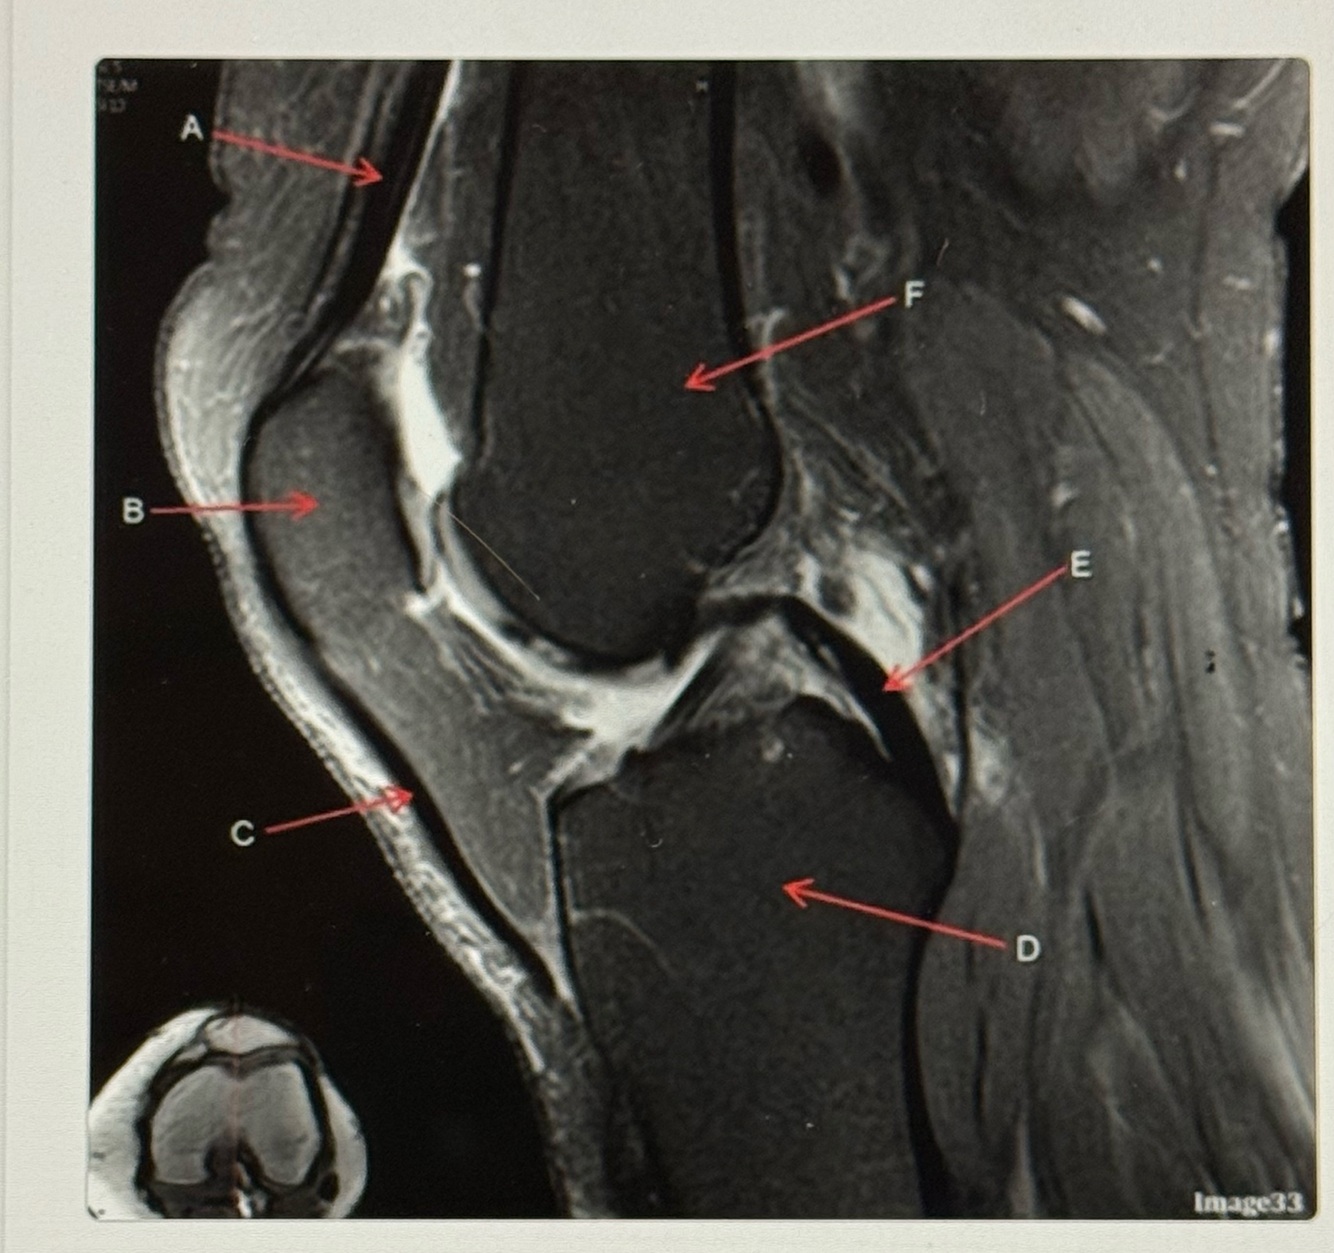

16

Q

Letter C points to the

A

Patellar tendon

17

Letter D points to the

Tibia

18

Letter E points to the

Posterior cruciate ligament (PCL)

19

Letter F points to the

Femur